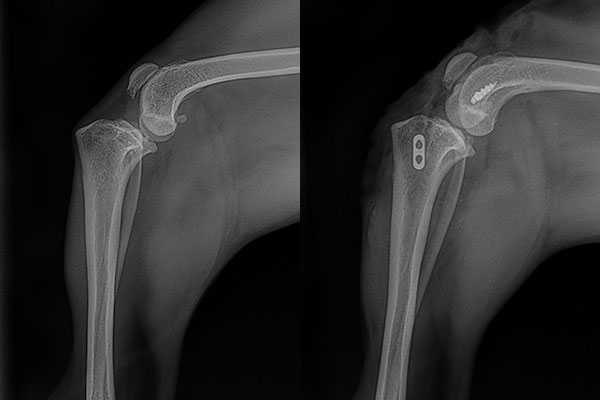

Before and after radiographs (X-rays) of an Anchor Lock surgical repair of a torn cranial cruciate ligament in a small dog. In the X-ray prior to surgery the cranial cruciate ligament is torn which allows the tibia (lower bone) to move forward and the femur (upper bone) to slide down the back side of the joint. After repair the surgical implants are visible and the femur has been restored to the normal position on top of the tibia.

Photos courtesy of Arthrex Vet Systems. © 2024-08 Arthrex, Inc. All rights reserved.